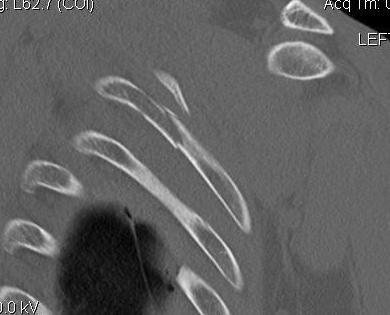

Scapular neck fracture with clavicle fracture

floatfloatfloat